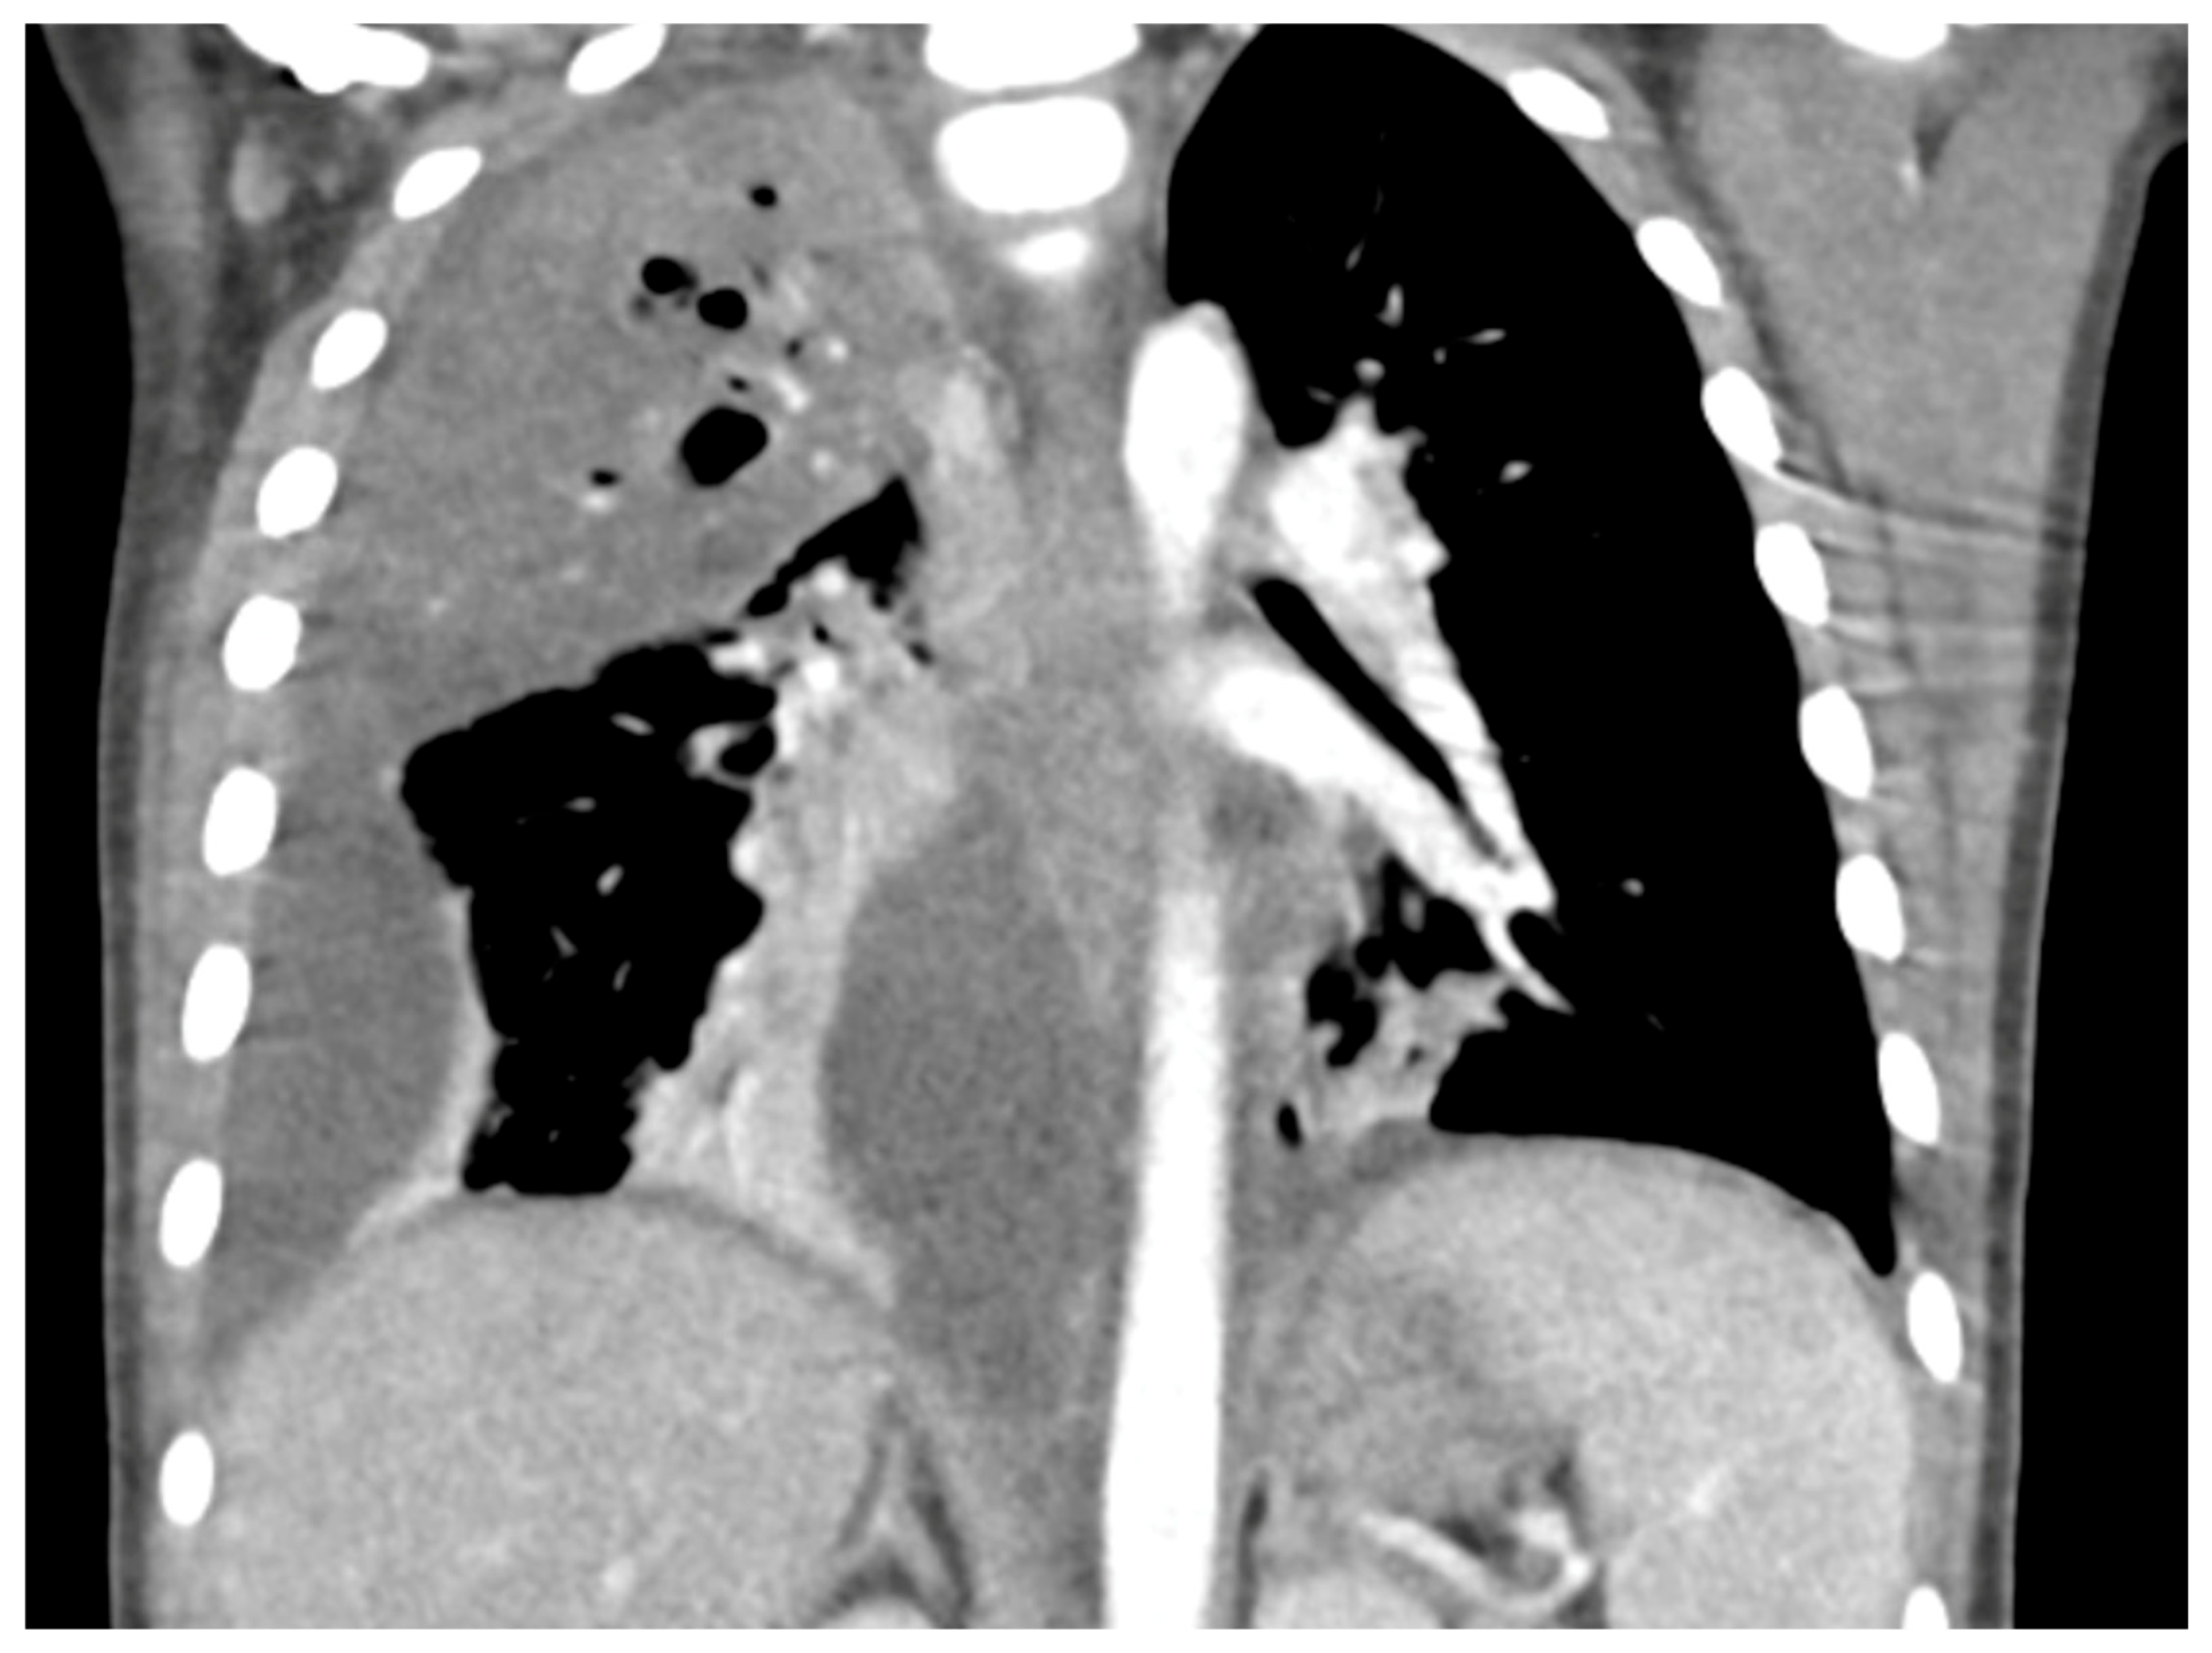

- Huang, W.E.; Matifoll, J.A.; Lord, D.; Haggie, S. A review of imaging in the diagnosis and management of complicated paediatric pneumonia. Paediatr. Respir. Rev. 2025, 54, 12–18. [Google Scholar] [CrossRef]

- Hoffer, F.; Bloom, D.; Colin, A.A.; Fishman, S.J. Lung abscess versus necrotizing pneumonia: Implications for interventional therapy. Pediatr. Radiol. 1999, 29, 87–91. [Google Scholar] [CrossRef]

- Hacimustafaoglu, M.; Celebi, S.; Sarimehmet, H.; Gurpinar, A.; Ercan, I. Necrotizing pneumonia in children. Acta Paediatr. 2004, 93, 1172–1177. [Google Scholar] [CrossRef]

- Tan Kendrick, A.P.; Ling, H.; Subramaniam, R.; Joseph, V.T. The value of early CT in complicated childhood pneumonia. Pediatr. Radiol. 2002, 32, 16–21. [Google Scholar] [CrossRef]

- Hodina, M.; Hanquinet, S.; Cotting, J.; Schnyder, P.; Gudinchet, F. Imaging of cavitary necrosis in complicated childhood pneumonia. Eur. Radiol. 2002, 12, 391–396. [Google Scholar] [CrossRef][Green Version]

- Carrard, J.; Bacher, S.; Rochat-Guignard, I.; Knebel, J.-F.; Alamo, L.; Meuwly, J.-Y.; Tenisch, E. Necrotizing pneumonia in children: Chest computed tomography vs. lung ultrasound. Front. Pediatr. 2022, 10, 898402. [Google Scholar] [CrossRef]

- Kurian, J.; Levin, T.L.; Han, B.K.; Taragin, B.H.; Weinstein, S. Comparison of ultrasound and CT in the evaluation of pneumonia complicated by parapneumonic effusion in children. Am. J. Roentgenol. 2009, 193, 1648–1654. [Google Scholar] [CrossRef] [PubMed]

- Lai, S.-H.; Wong, K.-S.; Liao, S.-L. Value of lung ultrasonography in the diagnosis and outcome prediction of pediatric community-acquired pneumonia with necrotizing change. PLoS ONE 2015, 10, e0130082. [Google Scholar] [CrossRef]